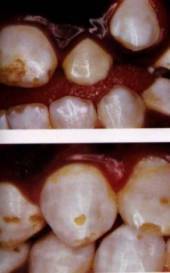

But less about other dangers, for the moment. We want to bring you images of dental fluorosis. They will act as a rough guide to the severity of your condition.

Six types of fluorosis (Source: Fluoride Free, Ireland):

Four pictures of fluorosis (Source: Fluoride: Protected Pollutant or Panacea? Canada):

Five pictures of fluorosis (source: Fluoride Action Network, USA):

Six pictures of fluorosis (source: Provided by Dr Susheela, India):